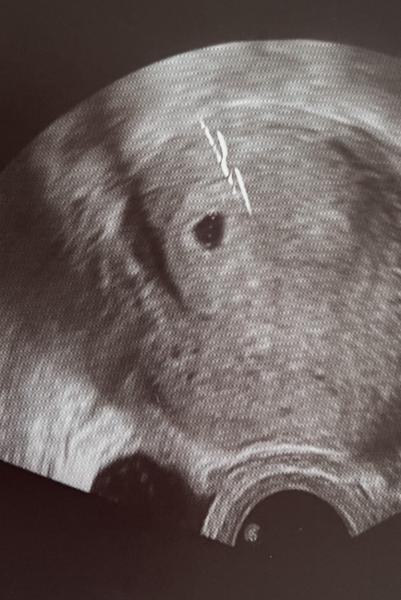

Huhu :) Ich hatte gestern mein 1. Ultraschall in Woche 5+3 und man konnte sehr gut die Fruchthöhle sehen jedoch leider kein Inhalt 🥲 bzw meinte die FÄ das man eine embryonale Anlage schon erahnen kann. Sie ist wirklich eine sehr tolle einfühlsame Ärztin ! Ich habe zu ihr gewechselt als mein Gyn so kalt“ war als ich meine Fehlgeburt in Woche 10 hatte im Oktober. Jedenfalls hatte ich in der SSW mit der Fehlgeburt schon zu dem Zeitpunkt ein Embryo gesehen 🥹 und diesmal eben nicht. Ich weiß alles Ultra früh aber denke ist verständlich mit meiner Vorgeschichte. Jedenfalls hab ich erst in 4 Wochen ein neuen Termin 😩 aber jetzt ist es eben so ungewiss… Das 1. Bild ist die FG 2. die jetzige

Bild zu Nur Fruchthöhle an SSW 5+3 - Schwanger - wer noch? Rund um die Schwangerschaft